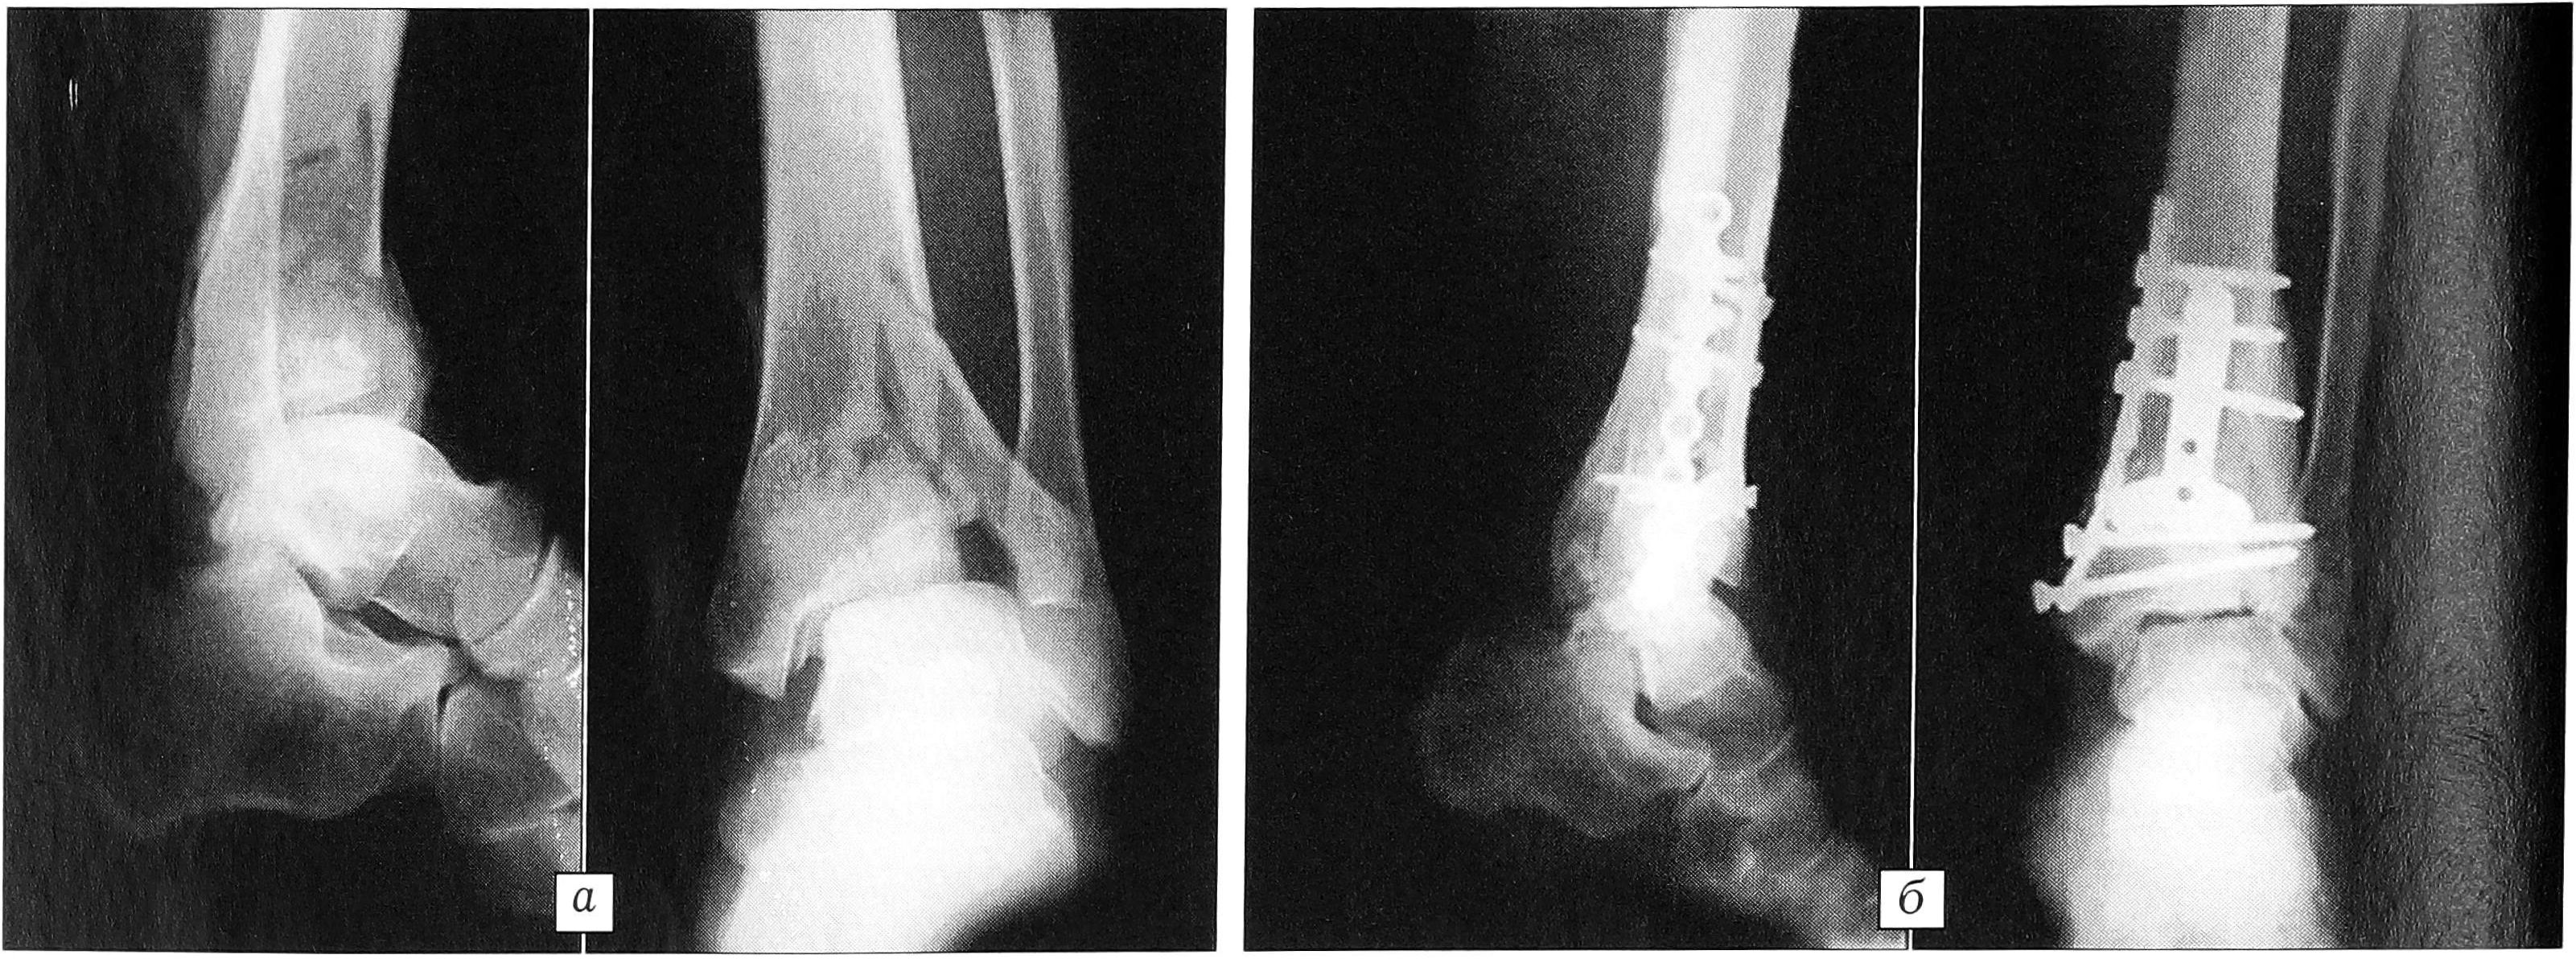

В качестве примера приводим рентгенограммы двух больных (рис. 2 и 3).

Рис. 3. Рентгенограммы больного К. 66 лет. Многооскольчатый компрессионный перелом дистального метаэпифиза большеберцовой кости (вариант Д). а — до операции; б — после остеосинтеза крупных фрагментов пластиной «лист клевера» и мелких свободных фрагментов пластиной для спицевинтовой фиксации.